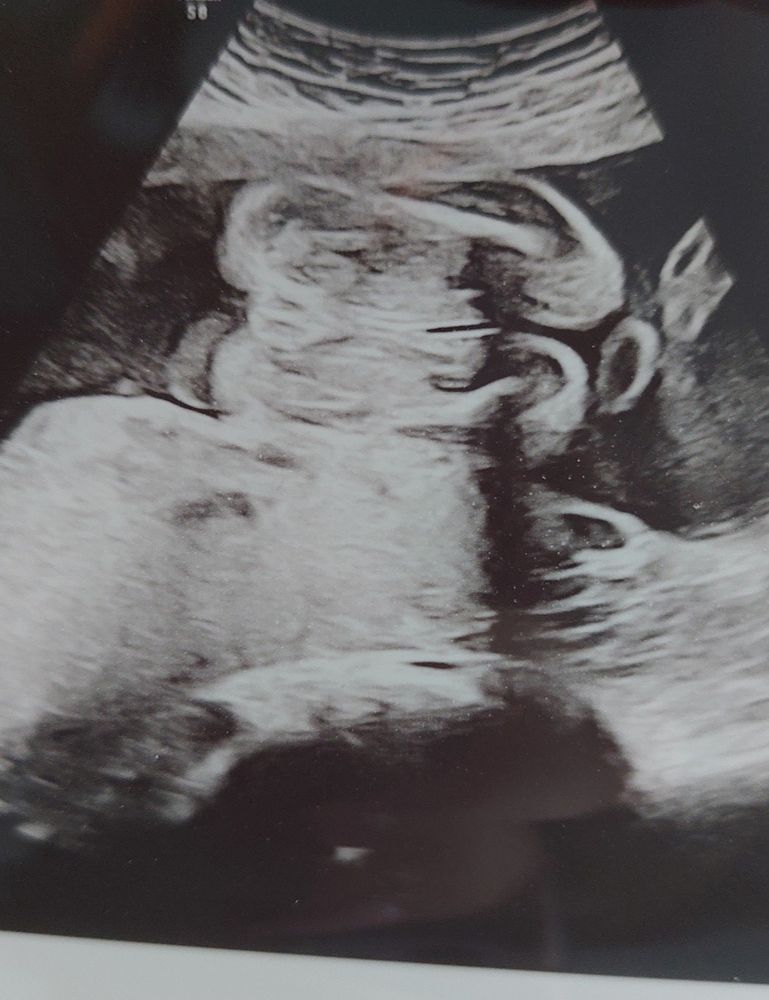

Узи. Пол ребёнка

Изображение

Всем привет! Первая моя беременность, на узи сказали что девочка, но всё равно есть какие-то сомнения. Буду рада если поделиться своими историями, были ли